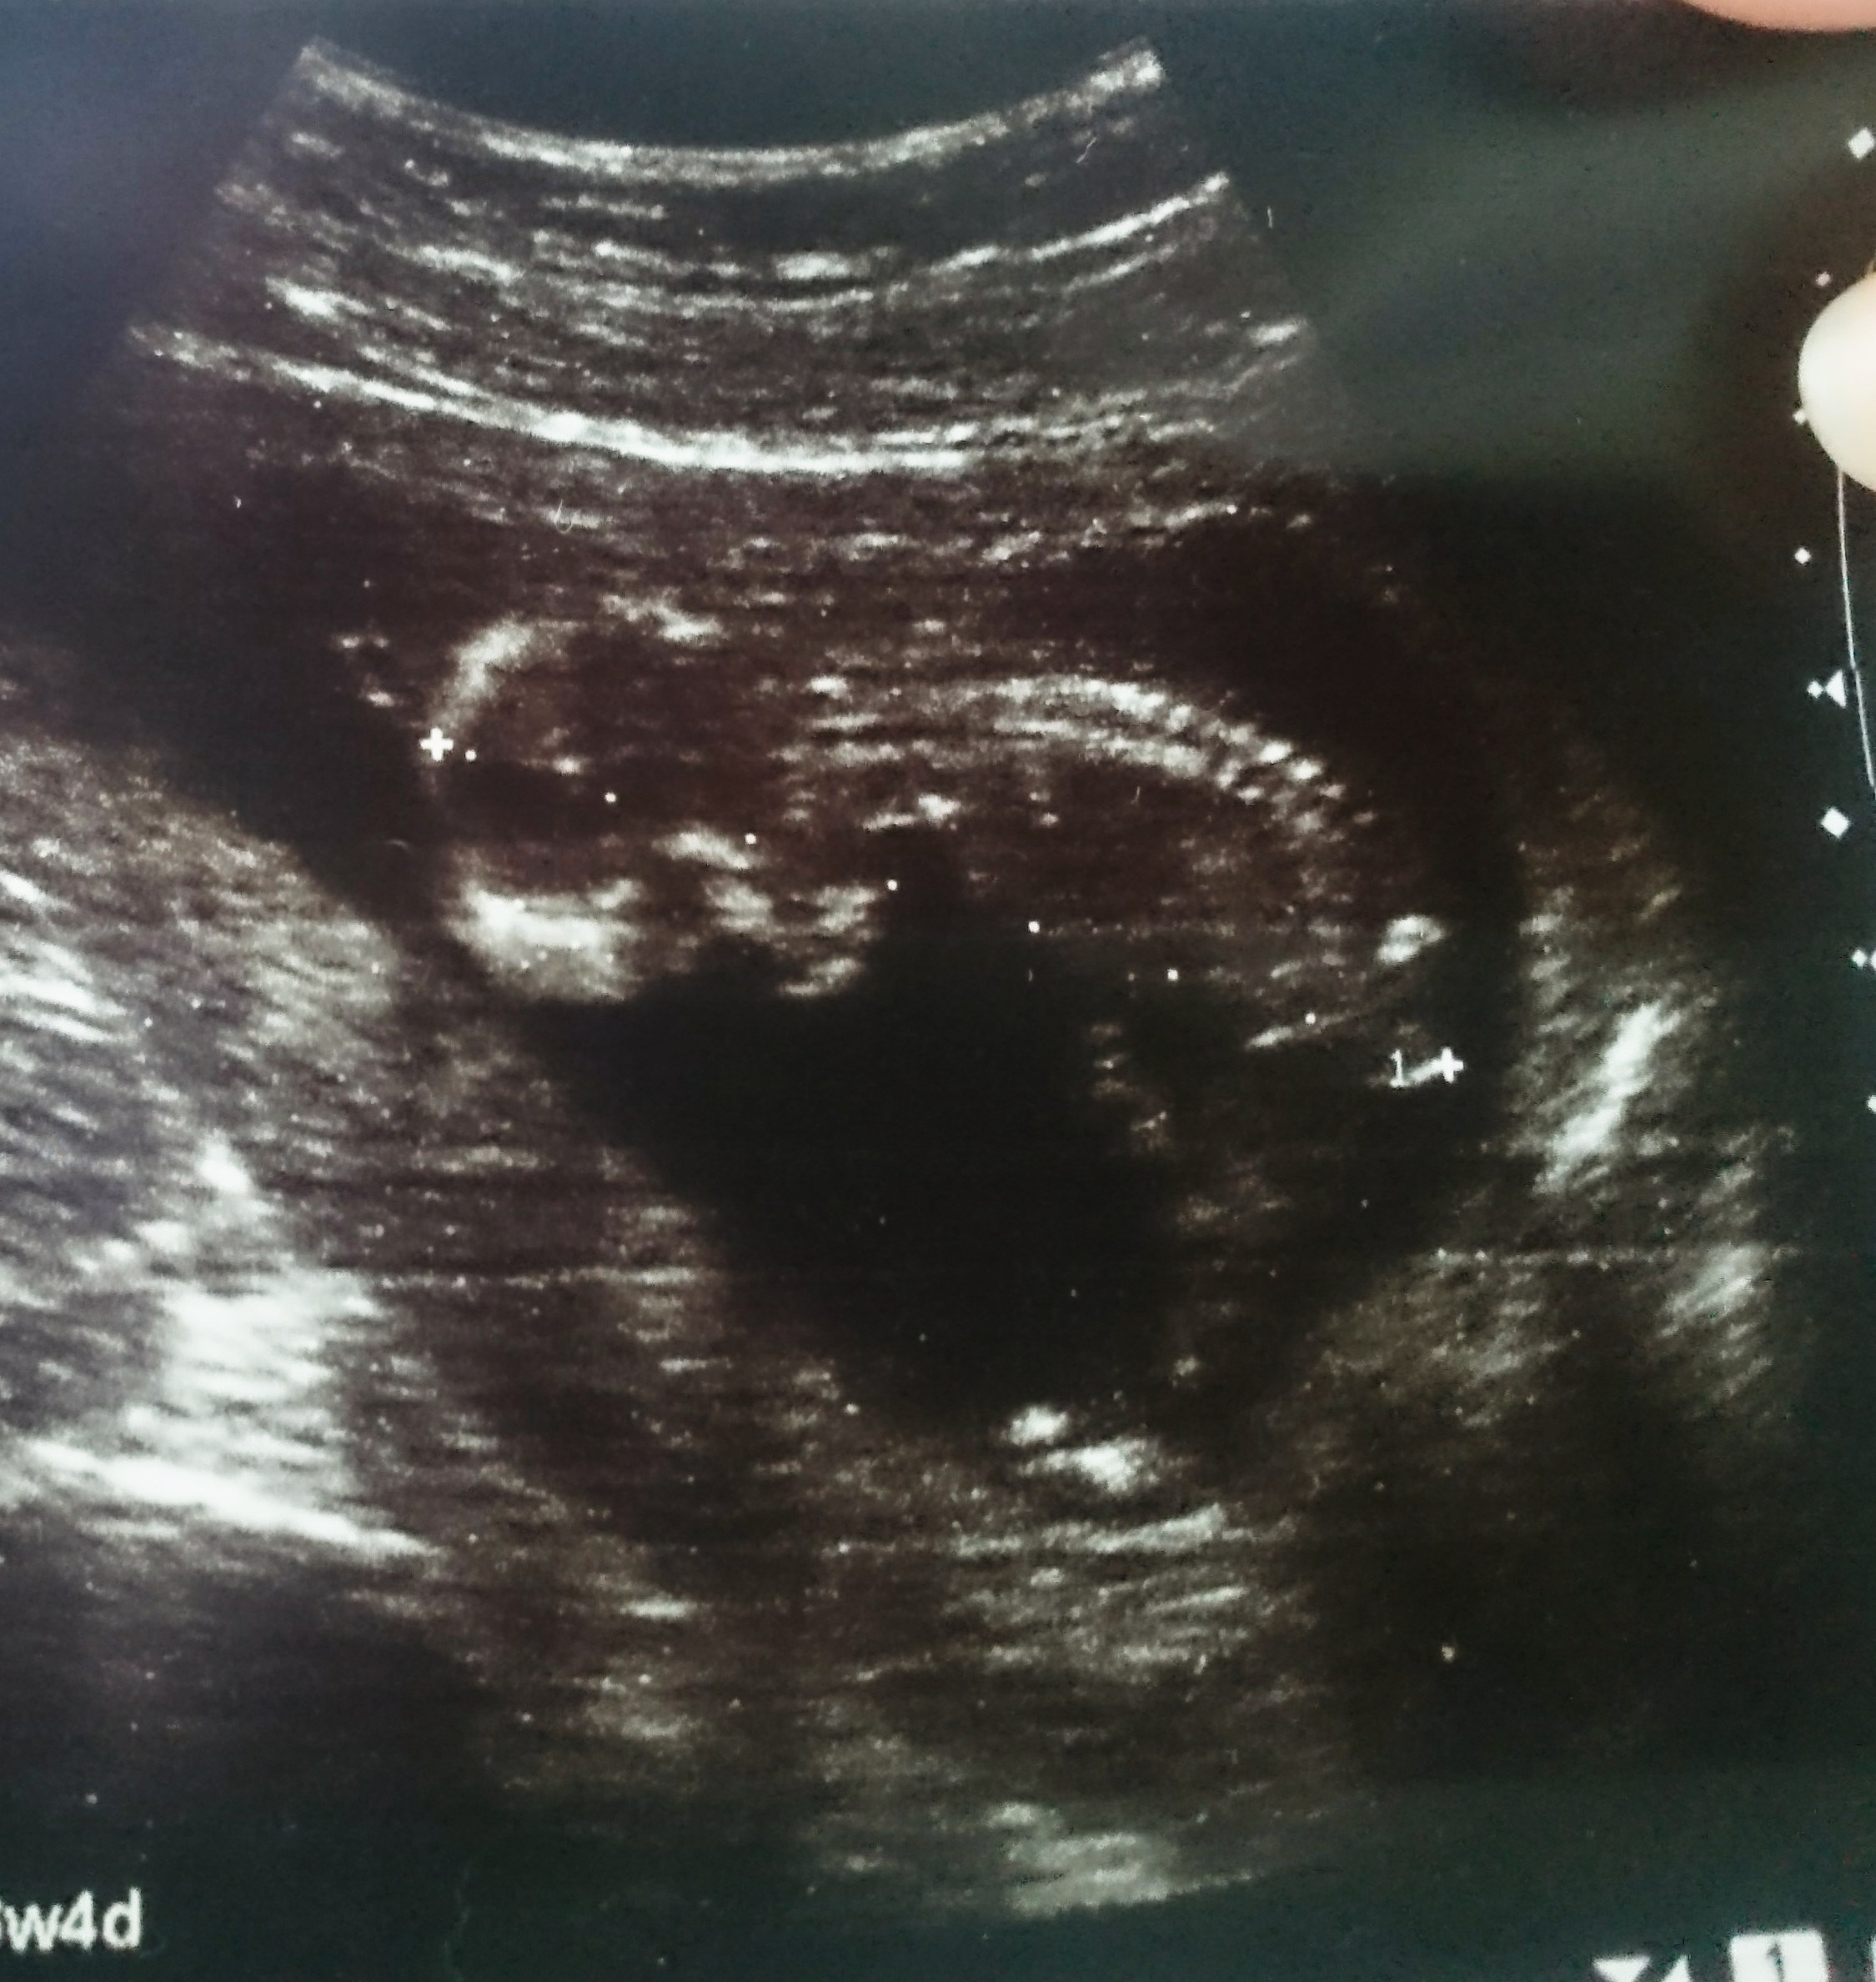

Cześć dziewczyny proszę was o ocenę zdjęcia usg... Miesiąc temu zapowiedzieli mi syna a 4 grudnia na połówkowym ze córka... Trochę mam mętlik w głowie 😞